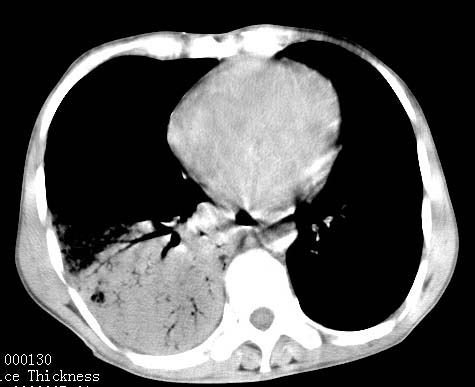

病人女 60岁 咳嗽 气促十余天,大叶性肺炎.

右肺上下叶均见 大片状密度增高影,边界清晰,其内可见支气管充气征,气管支气管通畅。纵膈略向右移位,其内无肿大淋巴结影。首先考虑炎性病变。不排除一些特异性的炎症。不知道发烧吗??wbc高吗??建议治疗后复查!!